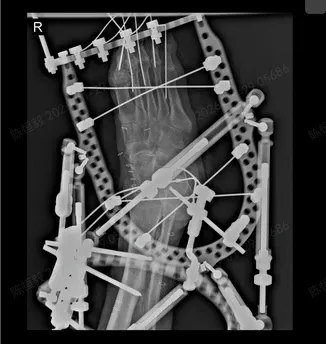

两院专家共同研读患者病历与检查报告,反复论证治疗方案,最终确定采用计算机辅助泰勒六轴空间外固定架进行矫正治疗。

该技术是当前复杂下肢畸形矫正的前沿手段,通过三维空间精准调控,可逐步调整足部力线与形态,避免传统手术创伤大、矫正精度不足的弊端,具有微创、安全、恢复快等显著优势,恰好适配患者的病情需求。

手术严格按照预设方案有序开展,专家团队凭借精湛的操作技巧,借助先进设备精准定位、分步矫正,成功为患者完成畸形修复与固定。

整个手术过程创伤小、出血少,未出现任何并发症,达到了预期治疗效果。